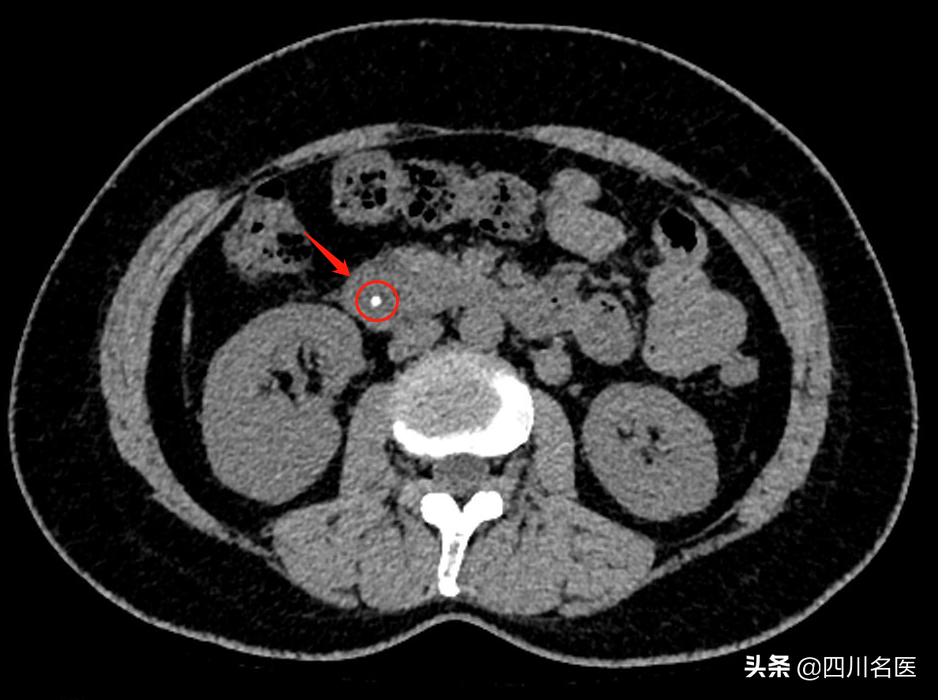

经过了CT检查,很快就找出了原因——胆总管卡着一颗大小约4mm的“石头” 。这个石头卡在胆汁与胰液的出口处,让程女士出现腹痛。

程女士的CT片子